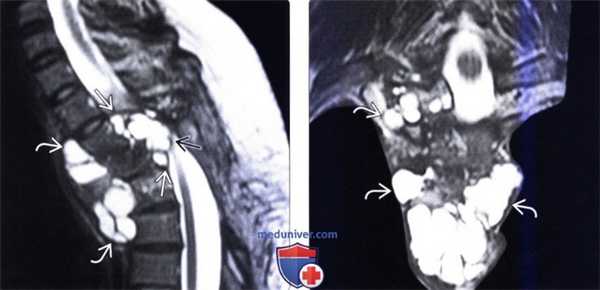

(Слева) Сагиттальный срез, Т2-ВИ: многокамерное кистозное образование, окружающее собой позвонки на уровне среднегрудного отдела позвоночника. Разрушение задней покровной пластинки стало причиной распространения кисты в вентральный отдел эпидурального пространства и сдавления спинного мозга. Твердая мозговая оболочка в подобных случаях обычно остается интактной.

(Справа) Фронтальный срез, Т2-ВИ: эхинококковая киста. Небольшие кисты отделяются от основной кисты, формируя новые кистозные образования. Процесс начинается в теле позвонка и может распространяться на дугу позвонка или смежные ребра.